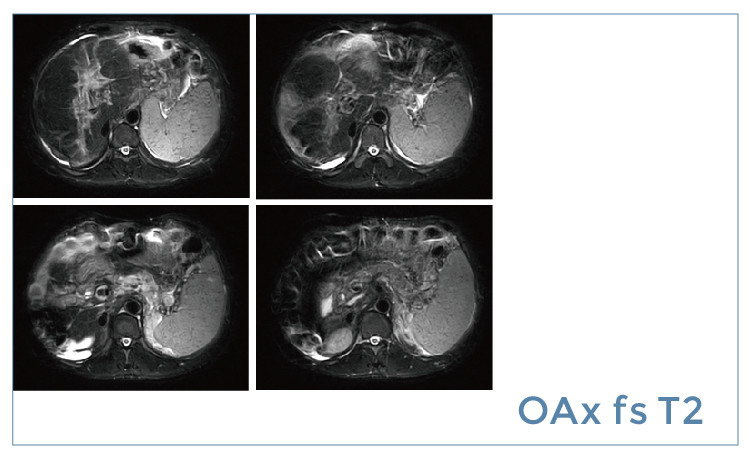

【朗润影像档案】20190517磁共振影像病例结果讨论